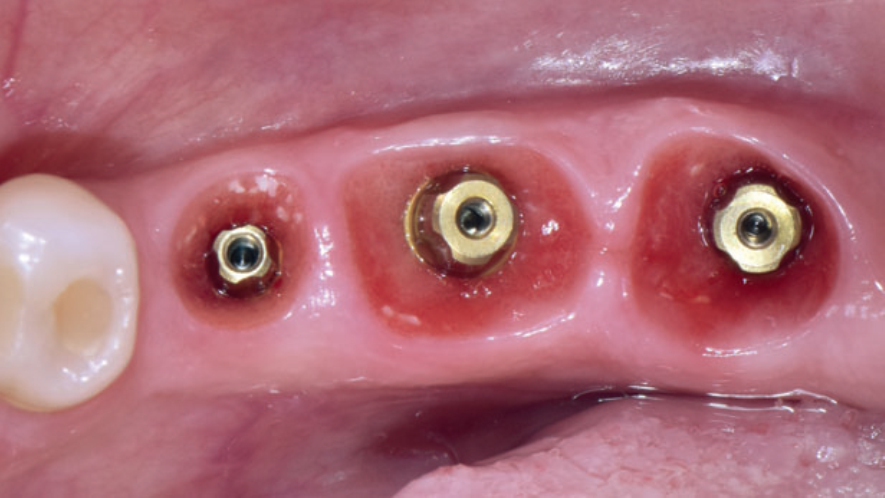

Ao serem instalados, os implantes que atingem um torque de inserção ≥ 32 Ncm podem ser imediatamente carregados com coroas unitárias de transição não oclusivas. Abaixo deste torque, ou em situações onde não desejamos correr riscos, em vez de uma coroa de transição, instala-se um cicatrizador personalizado contendo um perfil transmucoso com as mesmas características que a coroa provisória teria. Os objetivos dos cicatrizadores customizados nos casos de instalação do implante imediatamente após a exodontia são: selar o sítio cirúrgico respeitando o perfil do alvéolo de extração, estabilizar o coágulo sanguíneo e favorecer a regeneração óssea com o material substituto, evitar o colapso de tecidos moles durante o período de cicatrização e desenvolver um perfil de emergência protético ideal para a futura coroa sobre implante, baseado na anatomia do dente natural extraído, sem receber carga oclusiva.

Nos casos de instalação de implantes em regiões edêntulas, também é possível empregar cicatrizadores personalizados, desenvolvendo um perfil de emergência protético ideal para a futura coroa sobre implante, baseado na anatomia do dente natural ausente. Os dois procedimentos restabelecerão o perfil de emergência original do paciente durante a fase de cicatrização/osseointegração dos implantes, devolvendo a harmonia dentogengival, com a recuperação das papilas interdentais e a reconstituição do arco gengival côncavo, com altura adequada da margem em relação aos dentes adjacentes.

Quando corretamente indicados e executados, os cicatrizadores personalizados proporcionam bons resultados estéticos, biológicos e funcionais. A criação/manutenção de um perfil de emergência anatomicamente correto é um dos aspectos mais importantes para fornecer resultados estéticos e funcionais agradáveis às próteses implantossuportadas, tanto no setor anterior quanto no setor posterior.